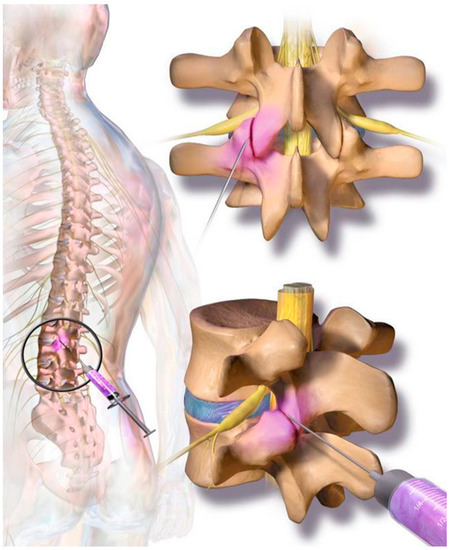

The cellular preparation of these fresh, autologous ADRCs was injected under para-articular fluoroscopic control on both sites of the individually affected facet joints. The joints in the adjacent segments were injected as well as the target segment (typically, L3 to L5 and L5/S1). The procedure was performed within the same session of fat tissue recovery, and preparation of the cells. Stem cell suspension was diluted with physiological saline to 1 mL per injected joint. At the Adipose-derived stem cell injection, contrast media was not employed due to unknown interaction with the regenerative cells. The injection was performed in prone position in the same fashion as the test injection. However, mild sedation was used for the final injection. The fat removal to injection procedure was typically finished in two to three hours (Figure 2). Patients were discharged from the outpatient clinic within four hours after beginning of the treatment. Pain medication was not recommended and not employed by the study population.

Figure 2.

On each level at the back of the spine, two small facet (zygapophyseal) joints—one from an upper and one from a lower vertebra—act as connectors to the spine and provide support as they allow the spine to bend and move. Facet joint syndrome significantly contributes to the high prevalence of back pain observed in western societies. Current therapies include local cortisone injections; however, there are mixed and negative reports regarding long-term efficacy for facet joint syndrome pain relief.